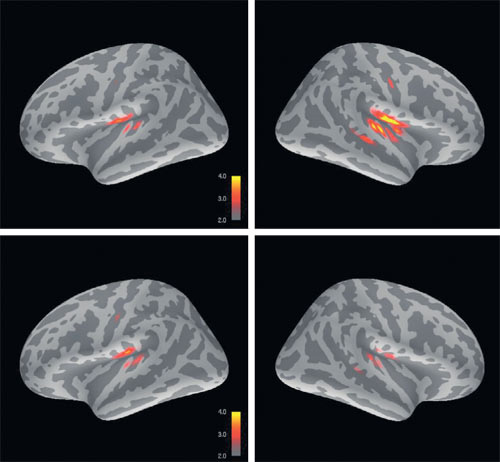

Обнаружить физиологический субстрат того, что раньше было доступно психиатрии только и исключительно в поведенческих проявлениях, значит найти потенциальную «мишень для вмешательства»: шанс на коррекцию. На снимках: МЭГ демонстрирует, что мозг ребёнка с аутизмом (внизу) реагирует на неожиданный звук иначе, чем в норме (вверху)